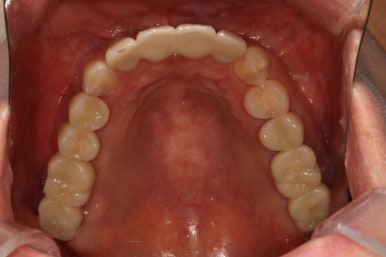

위턱 교합면입니다.

가장 드라마틱하게 바뀐 곳 중 하나인데요,

자기 자리를 잃어버렸던 치아들은 제거되고, 앞니는 지르코니아 크라운과 레진치료로 깨끗한 모습을 되찾았습니다.

썩었던 사랑니도 발치되었고 어금니 부위는 이제 깔끔한 스트라우만 임플란트 + 지르코니아 크라운 조합으로 마무리되었군요.